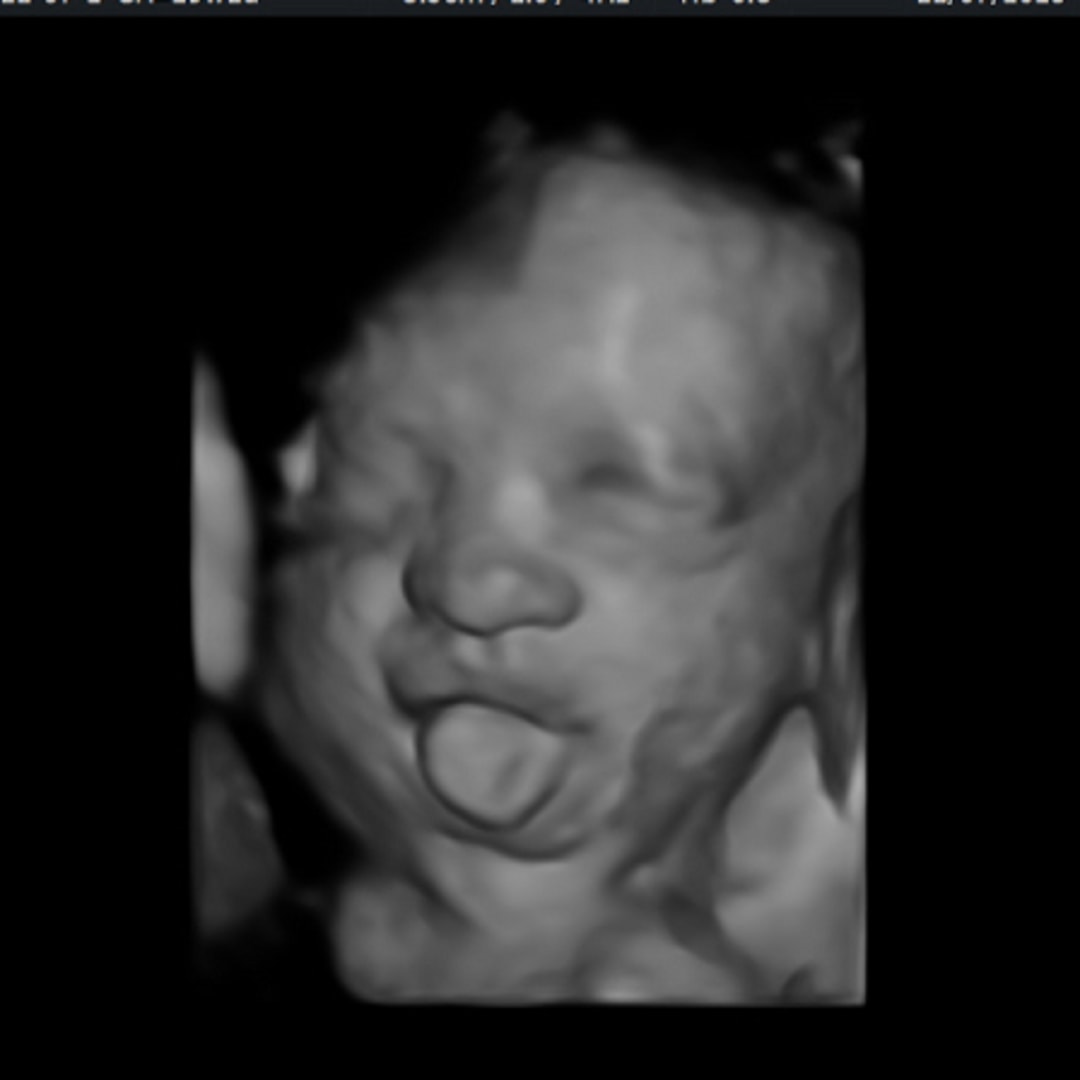

Baby Alara

Alara Mae

Momcozy Upgraded Adjustable Nursing Pillow